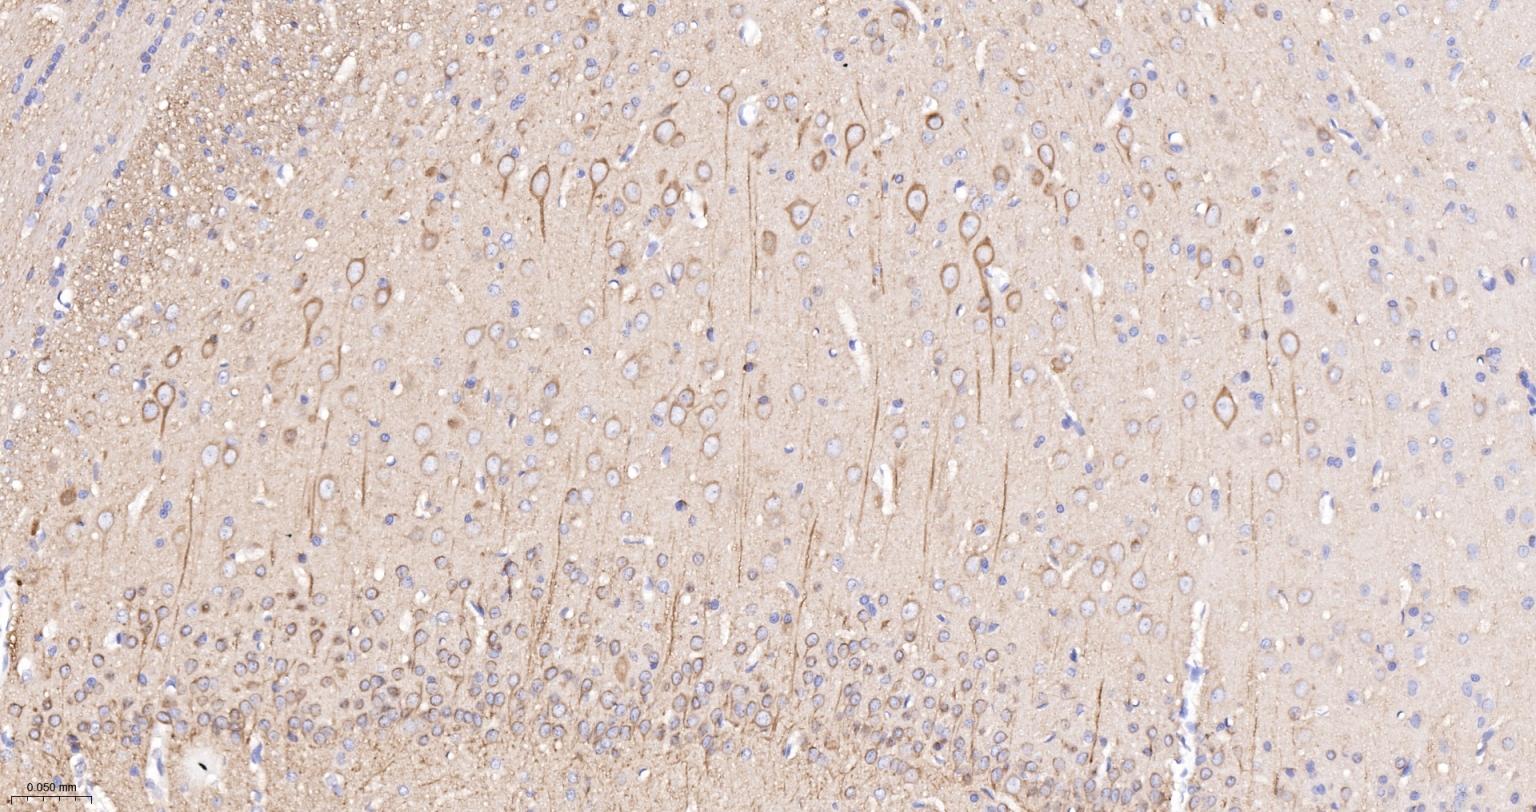

Paraformaldehyde-fixed, paraffin embedded (rat brain); Antigen retrieval by boiling in sodium citrate buffer (pH6.0) for 15min; Block endogenous peroxidase by 3% hydrogen peroxide for 20 minutes; Blocking buffer (normal goat serum) at 37°C for 30min; Incubation with (TUBB3 (Neuronal Marker) ) Monoclonal Antibody, Unconjugated (bsm-33177M) at 1:200 overnight at 4°C, followed by operating according to SP Kit(Mouse)(sp-0024) instructionsand DAB staining.

Paraformaldehyde-fixed, paraffin embedded (mouse brain); Antigen retrieval by boiling in sodium citrate buffer (pH6.0) for 15min; Block endogenous peroxidase by 3% hydrogen peroxide for 20 minutes; Blocking buffer (normal goat serum) at 37°C for 30min; Incubation with (TUBB3 (Neuronal Marker) ) Monoclonal Antibody, Unconjugated (bsm-33177M) at 1:200 overnight at 4°C, followed by operating according to SP Kit(Mouse)(sp-0024) instructionsand DAB staining.